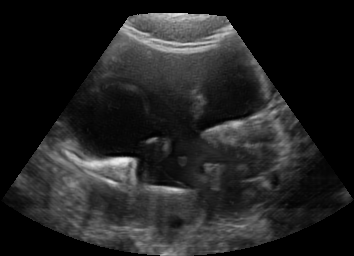

Real in-vivo images. 22 ultrasound sequences were collected using a GE Voluson E8 machine during standard fetal screening exams of 8 patients. Each sequence is several seconds long. We extracted all 4427 frames and resize them to , see Fig. 2 for some examples. The resulting image set was randomly split into training-validation-test sets by a 80-10-10% ratio.